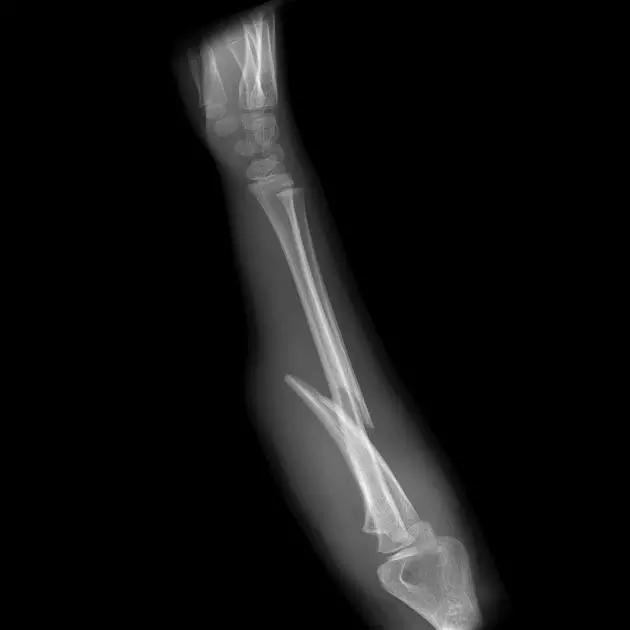

7. 浮膝

特指股骨、胫腓骨同时骨折,膝关节上下无附着而得名。其它浮髋、浮肩与此同理。

(来源:Medscape)

浮膝的 Fraser's 分型(来源:Management of the Floating Knee in Polytrauma Patients. Open Orthop J. 2015 Jul 31;9:347-55.)